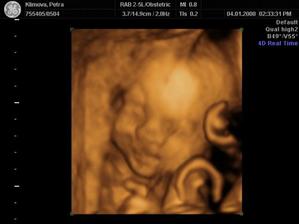

Katy+Naty

Tak se nám poštěstilo a s milovaným jsme počali dvojčátka, která by měla přijít na svět začátkem dubna, ale myslím, že to bude dřív, jak to u dvojek bývá. Pan Dr. nám potvrdil ve 20.tt, že to budou slečny🙂